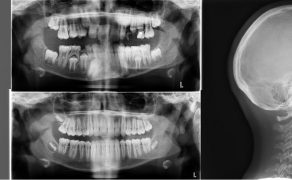

Cel. Celem pracy jest opis terapii ortodontycznej i czynnościowej pacjenta w późnym okresie uzębienia mlecznego, u którego rozpoznano: II klasę zębową i szkieletową podgrupy 2, brachycefaliczny typ wzrostu z wklęsłym profilem, ekstruzją górnych siekaczy centralnych i wychyleniem siekacza bocznego szczęki, nadmiernym napięciem mięśni żwaczy, parafunkcją zaciskania zębów i brakiem miejsca na stałe kły górne.

Opis przypadku. Artykuł opisuje leczenie 11-letniego pacjenta w późnym okresie uzębienia mlecznego, u którego rozpoznano: II klasę zębową i szkieletową podgrupy 2, brachycefaliczny typ wzrostu z wklęsłym profilem, ekstruzją górnych siekaczy centralnych i wychyleniem siekacza bocznego szczęki. W leczeniu zastosowano płytkę górną Schwarza ze śrubą trójkierunkową oraz urządzenie odciążające MFS złożone z relaksatora mięśniowego i płytki nagryzowej. Urządzenie odciążające jest efektywnym uzupełnieniem terapii ortodontycznej, wymusza długotrwałą pożądaną w terapii pracę mięśni zespołu ustno-twarzowego.